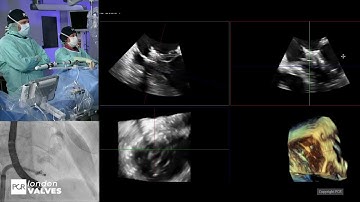

HEART Segmentation in D2P software. Customizes investigation of heart valves in 3D Segmentation .